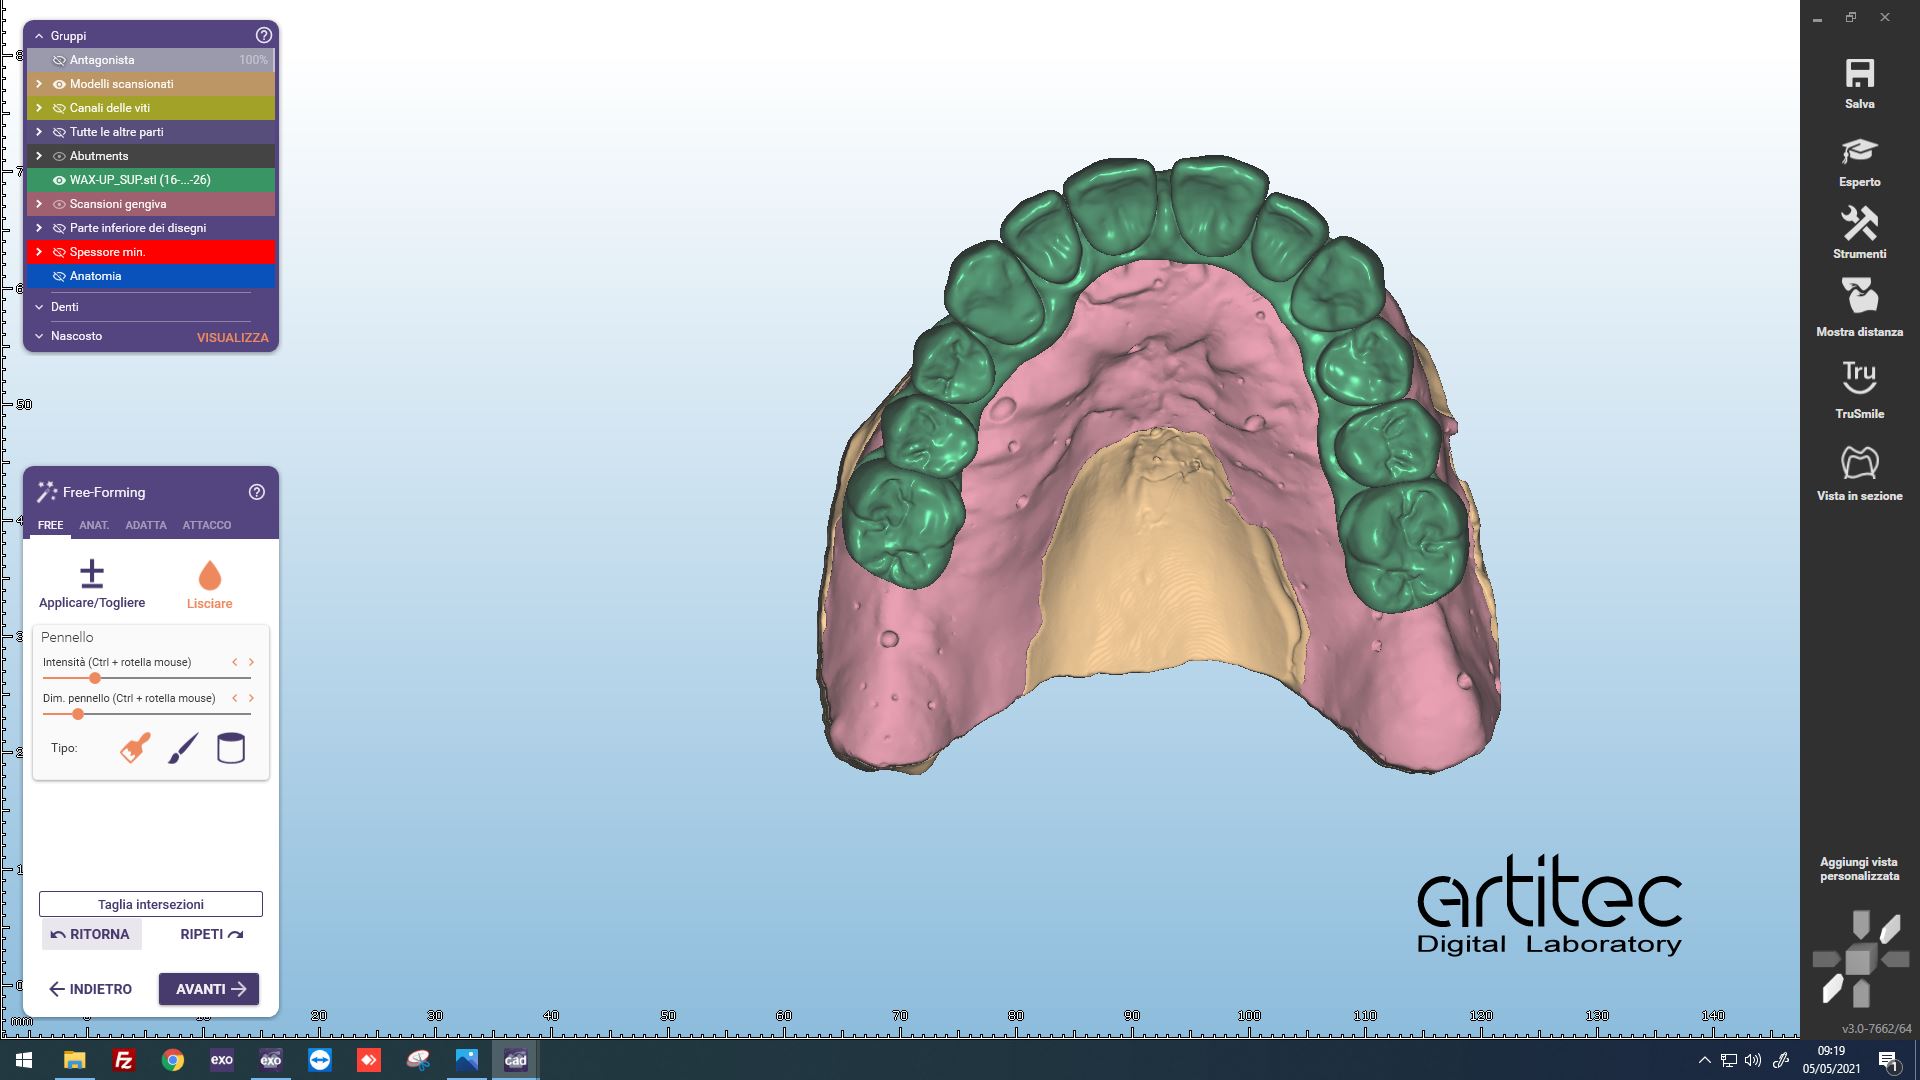

Fig. 10 Vista occlusale del progetto virtuale definitivo